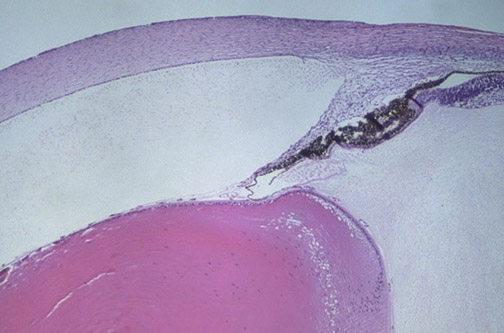

The structures of a fetal eye are seen here at low magnification, including the

cornea

, the

anterior chamber

crystalline lens

iris

ciliary body

, and the

sclera

.